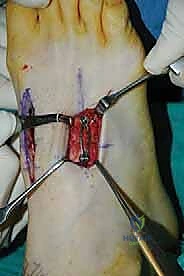

- "To further enhance stability and compression, we will now place compression staples. For the third TMT joint, we'll place a compression staple dorsally, spanning the fusion site."

* "And for the second TMT joint, another compression staple dorsally, spanning the fusion site between the second metatarsal and the intermediate cuneiform. This adds robust, broad-surface compression, particularly helpful in the midfoot."